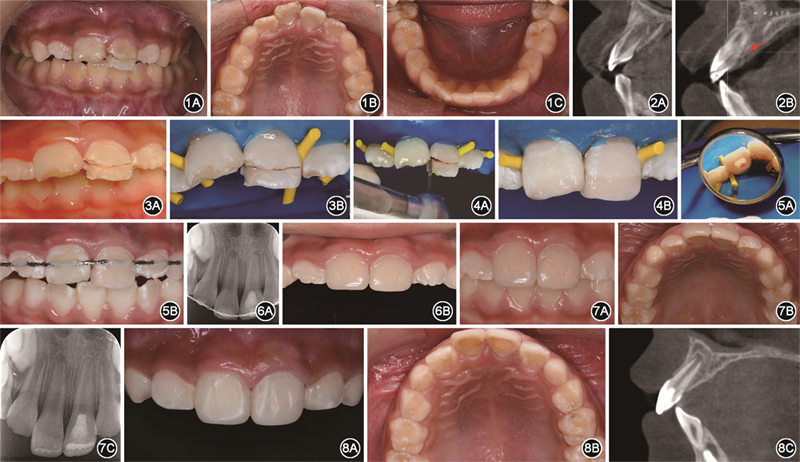

(1)一般情况:患儿女性,6岁,于2015年11月就诊于第四军医大学口腔医学院儿童口腔科,主诉上前牙外伤1 d伴疼痛不适感,求治。患儿家长代述患儿外伤后无头晕恶心呕吐,既往体健,无心脑血管疾病、传染病及药物过敏史。

(2)临床检查:见图1。患儿口腔卫生差,软垢(++)。为替牙列期,牙列式:16,55—53,12—22,63—65,26,36,73—75,32—42,83—85,46。11牙釉质和牙本质缺损伴轻度扭转,叩诊(+),探诊(-),松动Ⅰ度;21冠根折断,露髓,折裂线位于唇侧牙冠部,呈近远中向斜向腭侧牙根方向,唇侧折断片松动Ⅰ度,腭侧折断片松动Ⅲ度;12、22牙釉质缺损,未见明显松动。

面像;C:锥形束CT矢状位示牙根继续发育,切髓处可见牙本质桥形成(3)影像学检查:锥形束CT显示11、21牙根发育至Nolla 7期(图2A),21复杂冠根折,折裂线达牙槽嵴顶下约2 mm(图2B),11、12和22牙根未见明显根折影。

(1)上橡皮障:超声清洁12—22牙面(图3A),16、26和21局部浸润麻醉,上橡皮障(图3B)。

(2)唇侧初步固定:金钢砂车针沿折裂线去除薄壁弱尖(图4A),酸蚀,冲洗干燥,涂布粘接剂,流动树脂(7032A2,3M,美国)充填,精准复位腭侧折断片,光照20 s,完成初次固定修复(图4B)。

(3)腭侧深度切髓:腭侧开髓,揭髓室顶,深度达牙龈下约4 mm,去除冠髓和部分根髓(图5A),三氧化矿物凝聚体(mineral trioxide aggregate,MTA)(Dentsply,美国)盖髓,玻璃离子水门汀垫底(GC,日本)后流动树脂(7032A2,3M,美国)充填,弹性松牙固定(图5B),预约复诊。

(4)唇侧最终修复:术后1个月复诊,21临床及影像学检查(图6A)未见明显异常,拆除固定,11、21树脂修复(图6B)。

(5)术后6个月复诊:临床及影像学检查未见明显异常(图7)。

(6)术后24个月复诊:临床及影像学检查未见明显异常,牙根继续发育,根管壁增厚,切髓处可见牙本质桥形成(图8)。